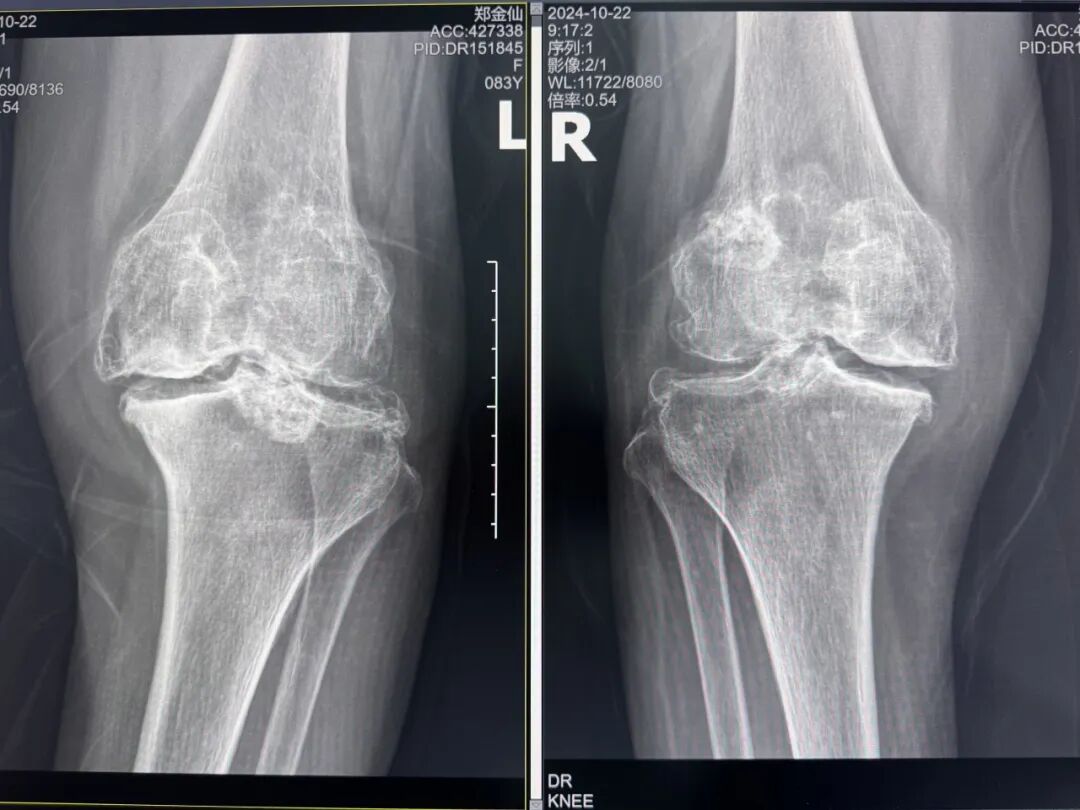

年輕時(shí)愛到處走走的鄭阿婆,晚年卻被雙膝劇痛困在輪椅上長(zhǎng)達(dá)二十年。經(jīng)羅副院長(zhǎng)診斷,她的膝關(guān)節(jié)軟骨幾乎磨光,關(guān)節(jié)嚴(yán)重畸形,呈"羅圈腿",走幾步便疼痛鉆心,連如廁都需家人抱扶。“我這輩子啊,估計(jì)再也站不起來了。”是阿婆最常說的話。

術(shù)前:AI通過CT掃描生成毫米級(jí)膝關(guān)節(jié)三維模型,為假體安裝設(shè)計(jì)出誤差小于1毫米的精準(zhǔn)方案 術(shù)中:智能導(dǎo)航系統(tǒng)如同"透視眼",引導(dǎo)醫(yī)生避開密集的神經(jīng)血管網(wǎng),截骨更精準(zhǔn),出血僅100ml 術(shù)后:當(dāng)天鄭阿婆即開始抬腿的康復(fù)訓(xùn)練,24小時(shí)內(nèi)扶助行器下地行走,三天后已能在病房走廊獨(dú)立行走,完成洗漱用餐 兩周后健步出院時(shí),女兒含淚感慨“之前擔(dān)心她年紀(jì)大扛不住手術(shù),沒想到恢復(fù)這么快!現(xiàn)在每天散步比我還精神。知道技術(shù)這么先進(jìn),真該早點(diǎn)來!”